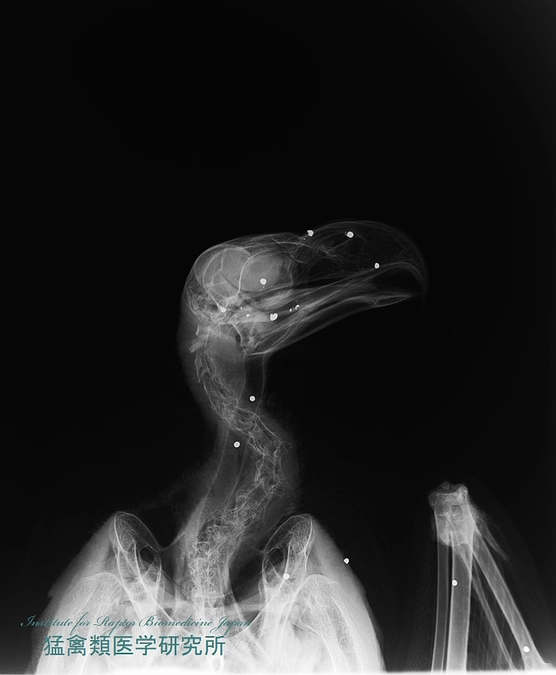

猛禽は狩猟の際に獲物に撃ち込まれた鉛弾を肉と一緒に飲み込んで鉛中毒になる。北海道で鉛弾の使用が禁止になったのは2000年から。しかし鉛中毒が発生しなかった年はこれまで一度もない。鉛弾規制のない本州から来るハンターが鉛弾を道内に持ち込み使っていることや、規制になっていない水鳥猟用の散弾が使われていることが原因と思われる。環境省は2025年から全国で鉛弾を規制する方針を打ち出しているが、ハンターが率先して無毒弾への切り替えを開始して欲しい!

鉛中毒に陥った個体はほとんど死体で収容され、生きて搬入されたものもほとんど助けることができない。多くの方に鉛中毒に苦しむオオワシの動画(2022年1月)をシェアしていただき、鉛中毒の恐ろしさを解っていただきたい!